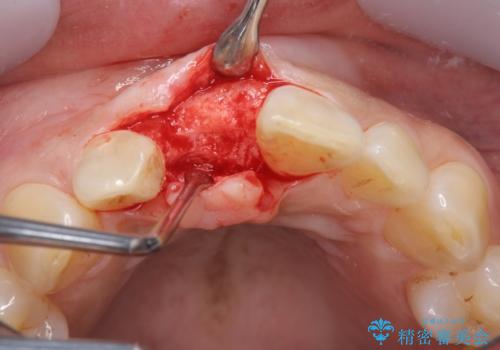

審美的・機能的に良好な位置に埋入するには、骨量が十分ではなかったため骨の造成を併用したインプラント埋入外科手術を行います。

前歯のインプラントを審美的に仕上げるには、インプラント周囲に十分な骨の量と厚みのある歯肉、そして埋入位置の精密な位置付けが重要です。